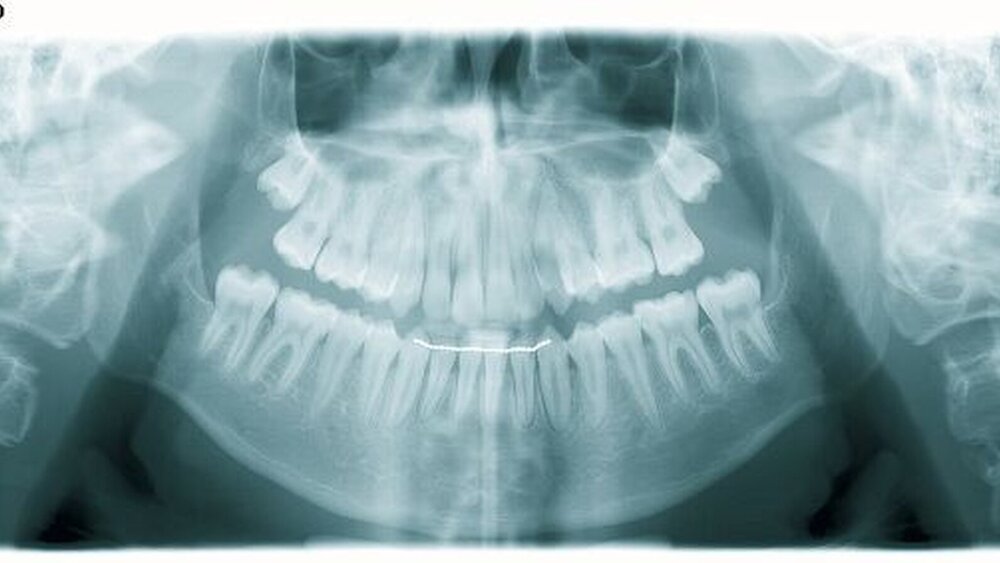

Die Beurteilung desOrthopantomogrammsergab keine Besonderheiten. Im Rahmen des Therapiekonzeptes ist nur zu vermerken, dass zu einem späteren Zeitpunkt eine Entfernung der Weisheitszähne sinnvoll erscheint und auch angewiesen wurde beziehungsweise wird.